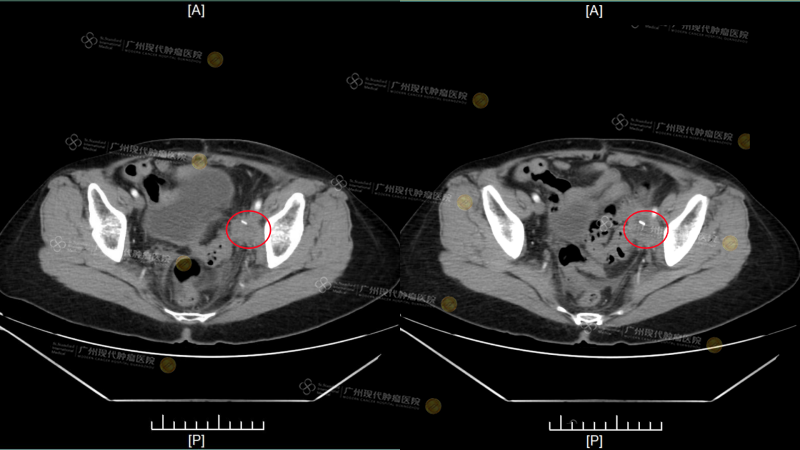

หลังจากปฏิเสธการรักษา ฟู อ้ายฉิน ดูราวกับยอมปล่อยวางความหวังทั้งหมดเธอเพียงต้องการใช้ชีวิตที่เหลืออยู่อย่างสงบให้มากที่สุด แต่ในเดือนสิงหาคม ปี 2025 ก้อนมะเร็งและความเจ็บปวดกลับถาโถมเข้ามาอีกครั้ง ต่อมน้ำเหลืองในอุ้งเชิงกรานกลับมาเป็นซ้ำและขยายใหญ่มีขนาดประมาณ 3.9 × 3.3 ซม.กดทับเส้นประสาทที่ขาส่งผลให้ขาซ้ายบวมอย่างรุนแรง ขณะเดียวกันตับก็พบรอยโรคแพร่กระจายใหม่ขนาดประมาณ 0.9 × 1.6 ซม. “ตอนนั้นฉันทำได้เพียงพึ่งยาแก้ปวดขนาดสูง เพื่อให้ตัวเองพอจะนอนหลับผ่านแต่ละวันไปได้” เธอกล่าวความเจ็บปวดและความสิ้นหวังอยู่เคียงข้างทั้งกลางวันและกลางคืนจนเธออดตั้งคำถามในคำอธิษฐานไม่ได้ว่า “ชีวิตที่เหลืออยู่ของฉัน จะต้องเป็นเช่นนี้ตลอดไปจริงหรือ?”

(CT ภาพนี้เป็นผลการตรวจขณะเข้ารับการรักษาในโรงพยาบาลของเรา เมื่อวันที่ 22 กันยายน)